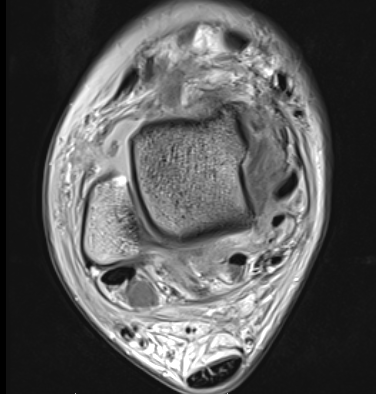

MRI

ATFL normal

Torn ATFL

CFL

PTFL

Deltoid ligament